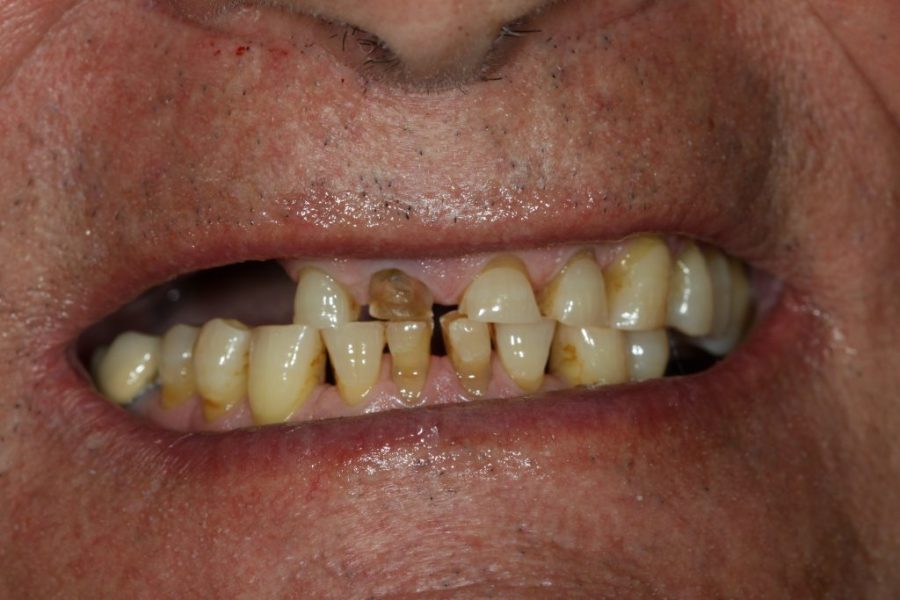

Henry’s Story: A Full Smile Makeover

Henry’s broken teeth were impacting his confidence. With a combination of root canal therapy, laser gum surgery, crowns, and dentures, we restored his smile over four weeks. Now, his family and grandchildren are thrilled with his transformation.